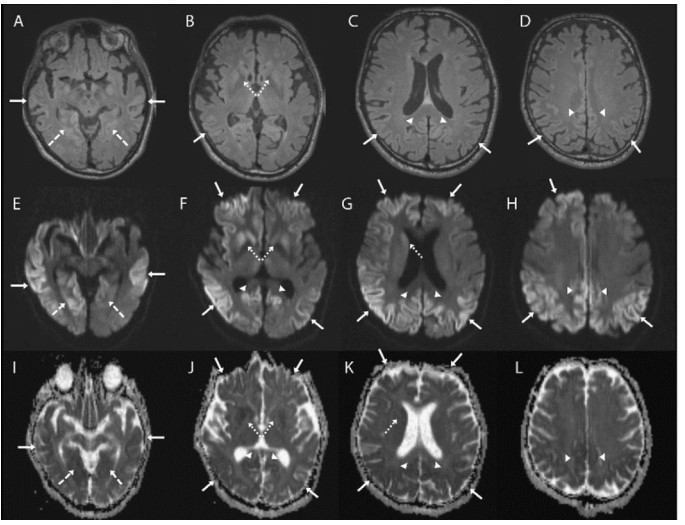

MRI imaging may reveal cortical gyral hyperintensities, more prominently seen in T2 and FLAIR sequences. This is described as cortical ribboning. Besides these, basal ganglia hyperintensities on T2-weighted sequences can also be seen in the early stages. The signal increase in CJD may also be seen in the hippocampus, thalamus, and mesencephalon.

Axial brain MRI sequences in a patient with sporadic Jakob-Creutzfeldt disease. Note that the axial fluid-attenuated inversion recovery (FLAIR) sequences (A–D) are generally much less sensitive than the diffusion sequences, particularly diffusion-weighted imaging (DWI) (E–H) and the apparent diffusion coefficient (ADC) map (I–L). The DWI and ADC map show cortical ribboning (solid arrows) in the bilateral parietal, right greater than left frontal and lingula (dashed arrows), and posterior cingulate (arrowheads). Asymmetric involvement of the striatum is also shown (right greater than left) (dotted arrows). Bright regions on DWI are dark on the ADC map, indicating true restricted diffusion of water molecules.

A brain MRI of the patient revealed a cortical-ribboning pattern with mild asymmetry and left caudate head hyperintensity. EEG showed intermittent sharp-wave complexes which were quasi-periodic along with slowing of background activity. Other routine blood biochemical tests were normal; lumbar puncture was not done as consent was not obtained.